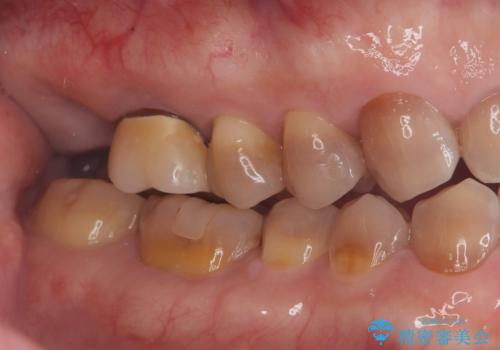

根尖性歯周炎|歯根嚢胞|インプラント治療

- 治療計画

- 右上7番に瘻孔を認め、根管治療を実施しましたが、瘻孔が再発し治癒が得られなかったため、抜歯のうえインプラントによる補綴治療を行いました。

抜歯と歯根嚢胞の除去を行った後、インプラントで治療しました。治療後は「自分の歯のように咬める」と大変ご満足いただけました。